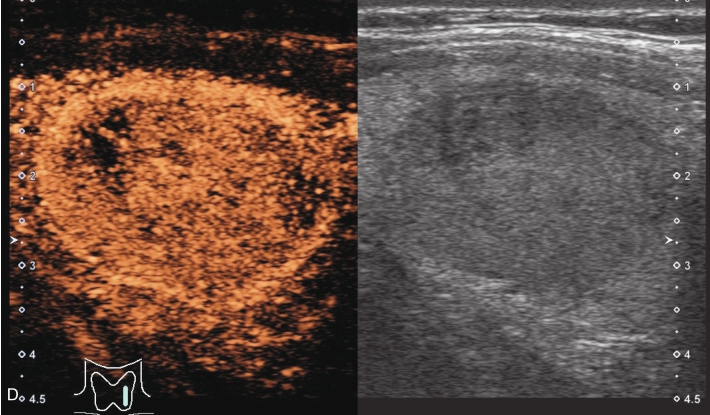

甲状腺形态基本正常,甲状腺实质回声稍增粗,分布尚均匀,甲状腺包膜尚光滑。甲状腺两叶内见多发结节,较大者位于左叶上极,呈类椭圆形,边界清楚,形态规则,纵横比<1,内部回声均匀,未见钙化,后方回声稍增强。CDFI显示左叶较大结节边缘可见丰富的条状血流信号,内部可见条状、点状血流信号,见图1-3-7。

图1-3-7 结节性甲状腺肿常规超声表现

A.常规超声图像;B.CDFI超声图像

甲状腺左叶上极较大结节增强早期呈稍高增强,自结节外周向中央灌注,增强晚期呈等增强,结节内部可见不均匀低增强区,见图1-3-8、ER1-3-4。

图1-3-8 结节性甲状腺肿超声造影图像

ER1-3-4 结节性甲状腺肿的超声造影

结节性甲状腺肿超声造影表现为病变多与周围正常甲状腺组织呈同步等或高增强,增强多较均匀,伴有囊性变者,内部可见无增强区,增强后结节边界清,周边可见环状增强,增强晚期呈等或稍高增强,也可呈稍低增强。

多早于周围正常甲状腺组织增强,从周边向中心快速充盈,呈均匀性高增强,增强后结节边界清,形态较规则,周边亦可见环状增强。

造影后结节大多呈同进或慢进,以不均匀性低增强多见,也可呈等或高增强,增强后结节边界不清,形态不规则,增强晚期可呈低增强或等增强。

图1-3-10 结节性甲状腺肿超声造影图

A.增强早期结节呈同步不均匀性等增强;B.增强晚期呈不均匀性低增强